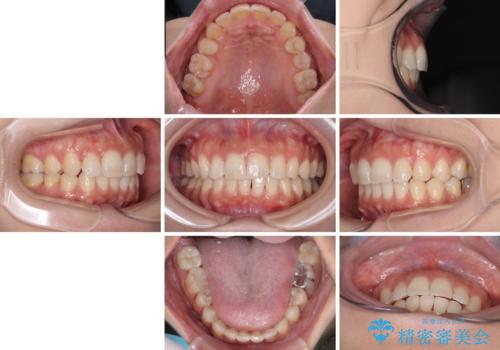

上顎の正中位置をほぼ保った状態で、綺麗に仕上げることができました。